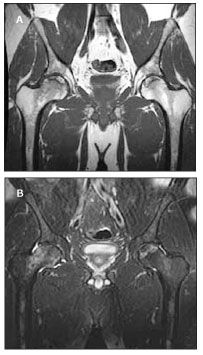

A 43-year-old white man with a 5-year history of HIV infection presented with a 2-week history of right upper thigh pain. His CD4+ cell count was 430/µL (43%), and his HIV RNA level was below 50 copies/mL. Antiretroviral therapy included abacavir, tenofovir, and ritonavir-boosted atazanavir. Findings on bilateral hip radiographs were normal. Three weeks later, after his pain persisted, an MRI scan revealed bilateral femoral head osteonecrosis (Figure 1).

Figure 1. T1-weighted (A) and T2-weighted (B) MRI scans of bilateral hips of patient described in Case 4, showing serpiginous lines of dark signal within the femoral heads and moderate bone marrow edema in the right femoral neck, consistent with osteonecrosis.

Repeated hip radiographs at that time showed smudging of the bilateral femoral heads, consistent with early osteonecrosis. The patient underwent right hip core decompression, which was unsuccessful in controlling his pain. He subsequently underwent a right total hip replacement a few months later after suffering unrelenting pain (Figure 2). His CD4+ cell count nadir was 282/µL (30%) reported 3 years before the onset of symptoms. The patient had taken a PI for 6 years. No risk factors for osteonecrosis were noted.